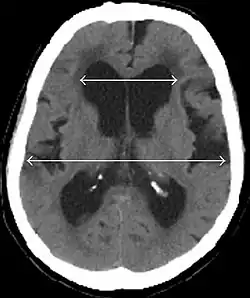

Evan's index is the ratio of maximum width of the frontal horns to the maximum width of the inner table of the cranium. An Evan's index more than 0.31 indicates hydrocephalus.[19]

Typical imaging findings in normal pressure hydrocephalus versus brain atrophy.[21]

Normal pressure hydrocephalus Brain atrophy

Preferable projection Coronal plane at the level of the posterior commissure of the brain.

Modality in this example CT MRI

CSF spaces over the convexity near the vertex (red ellipse ) Narrowed convexity ("tight convexity") as well as medial cisterns Widened vertex (red arrow) and medial cisterns (green arrow)

Callosal angle (blue V) Acute angle Obtuse angle

Most likely cause of leucoaraiosis (periventricular signal alterations, blue arrows ) Transependymal cerebrospinal fluid diapedesis Vascular encephalopathy, in this case suggested by unilateral occurrence

MRI scans are the preferred imaging. The distinction between normal and enlarged ventricular size by cerebral atrophy is difficult to ascertain. Up to 80% of cases are unrecognized and untreated due to difficulty of diagnosis.[22] Imaging should also reveal the absence of any cerebral mass lesions or any signs of obstructions. Although all patients with NPH have enlarged ventricles, not all elderly patients with enlarged ventricles have primary NPH. Cerebral atrophy can cause enlarged ventricles, as well, and is referred to as hydrocephalus ex vacuo. For these reasons it's utmost important to note that Evan's index although commonly used in imaging is not very specific for NPH. One recent systematic review and meta-analysis suggests that callosal angle has high diagnostic performance and is commonly used together with Evan's index.[23]